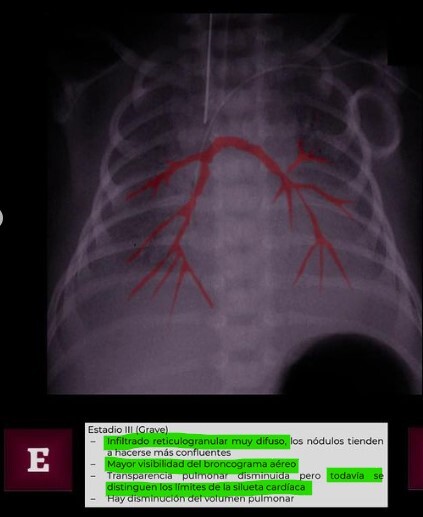

Q

SDR Estadio lll

A

• Infiltrado muy difusio , pero todavia se logra ver silueta cardiáca